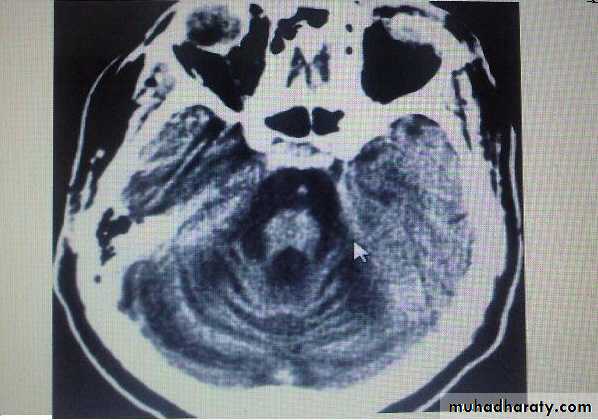

Group of heterogeneous inherited disorders characterized by slowly progressive cerebellar ataxia that affects gait early and severely and may eventually confine the patient to bed. They show considerable clinical variability .Most of them begin in adulthood. Atrophy of the cerebellum and sometimes also of the brainstem may be apparent on CT or MRI scans. Definitive diagnosis is by genetic testing. Treatment is symptomatic.

SCA showing atrophy of cerebellum.